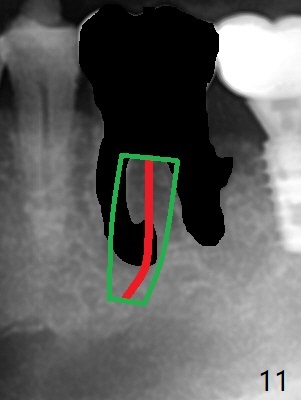

Venopuncture is conducted (Fig.1) for PRF and sticky bone (cortical chip and .5 cc ß-TCP). After use of proximators at #19, cowhorn forceps are applied, resulting in metal crown dislodgement. Since there is distal bone loss, distal socket sheath is contemplated. The tooth is sectioned. When an elevator is inserted between the roots, the distal root is loosened first. The 2 roots are removed, revealing a rounded end septum (Fig.2 S) and a larger distal socket. To avoid osteotomy deviation over the septum, a 12 mm bone trimmer is used, followed by point drill (Fig.3 *). But the lower half of the implant is deviated mesial (Fig.4) with decreased torque (~ 10 Ncm). To overcome this misfortune, the roots should not be removed until osteotomy is finished. Dual zones of bone graft is conducted. Sticky bone is placed until the plateau of the implant with a healing screw in place (Fig.4 * (bone zone)). After placement of a pair abutment, the same bone graft is packed until the margin of the abutment (Fig.5 * (soft tissue zone)). An immediate provisional is fabricated to close the socket with a piece of PRF as well. Fig.6-11 explains why the lower half of the implant deviates to the mesial socket, while Fig.12-16 illustrates how to prevent the deviation. After extraction of #19 (Fig.6,7), the crest of the septum is flattened (Fig.8 arrowhead) to prevent the initial deviation (Fig.9 red line). When a drill reaches a space (a socket, mesial in this case), the drill is deflected to the least resistant area (Fig.10 a bent red line), leading to the implant deviation apically (Fig.11 green). To prevent the apical deviation, therefore, the roots of the affected tooth is temporarily not removed (Fig.12). The osteotomy should not deviates with surgical guide because of similar density between the tooth and the bone (Fig.13). When the osteotomy is finished (Fig.14), the roots are extracted (Fig.15). The implant to be placed should not have deviation (Fig.16 green). The papillae are maintained by the immediate provisional 11 days postop (Fig.17). The incompletely seated abutment at #18 (Fig.5 <) is reseated completely 6 months postop (Fig.18). Crestal bone forms distal to #19 implant. There is no bone loss 4 months and 3 years 1 month post cementation at #19 and 18, respectively (Fig.19,20).